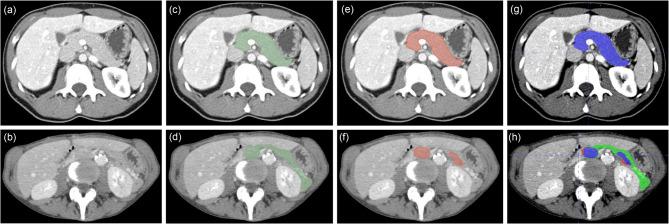

Accurate and fully automated pancreas segmentation is critical for advancing imaging biomarkers in early pancreatic cancer detection and for biomarker discovery in endocrine and exocrine pancreatic diseases. We developed and evaluated a deep learning (DL)-based convolutional neural network (CNN) for automated pancreas segmentation using the largest single-institution dataset to date (n = 3031 CTs). Ground truth segmentations were performed by radiologists, which were used to train a 3D nnU-Net model through five-fold cross-validation, generating an ensemble of top-performing models. To assess generalizability, the model was externally validated on the multi-institutional AbdomenCT-1K dataset (n = 585), for which volumetric segmentations were newly generated by expert radiologists and will be made publicly available. In the test subset (n = 452), the CNN achieved a mean Dice Similarity Coefficient (DSC) of 0.94 (SD 0.05), demonstrating high spatial concordance with radiologist-annotated volumes (Concordance Correlation Coefficient [CCC]: 0.95). On the AbdomenCT-1K dataset, the model achieved a DSC of 0.96 (SD 0.04) and a CCC of 0.98, confirming its robustness across diverse imaging conditions. The proposed DL model establishes new performance benchmarks for fully automated pancreas segmentation, offering a scalable and generalizable solution for large-scale imaging biomarker research and clinical translation.

准确且完全自动化的胰腺分割对于推进早期胰腺癌检测中的成像生物标志物以及内分泌和外分泌胰腺疾病的生物标志物发现至关重要。我们使用迄今为止最大的单机构数据集(n = 3031例CT)开发并评估了一种基于深度学习(DL)的卷积神经网络(CNN)用于自动化胰腺分割。由放射科医生进行真实分割,通过五折交叉验证用于训练3D nnU-Net模型,生成一组表现最佳的模型。为了评估泛化能力,该模型在多机构的AbdomenCT-1K数据集(n = 585)上进行了外部验证,专家放射科医生新生成了该数据集的体积分割并将公开提供。在测试子集(n = 452)中,CNN实现了0.94(标准差0.05)的平均骰子相似系数(DSC),表明与放射科医生标注的体积具有高度空间一致性(一致性相关系数[CCC]:0.95)。在AbdomenCT-1K数据集上,该模型实现了0.96(标准差0.04)的DSC和0.98的CCC,证实了其在不同成像条件下的稳健性。所提出 的DL模型为完全自动化胰腺分割建立了新的性能基准,为大规模成像生物标志物研究和临床转化提供了一种可扩展且可泛化的解决方案。